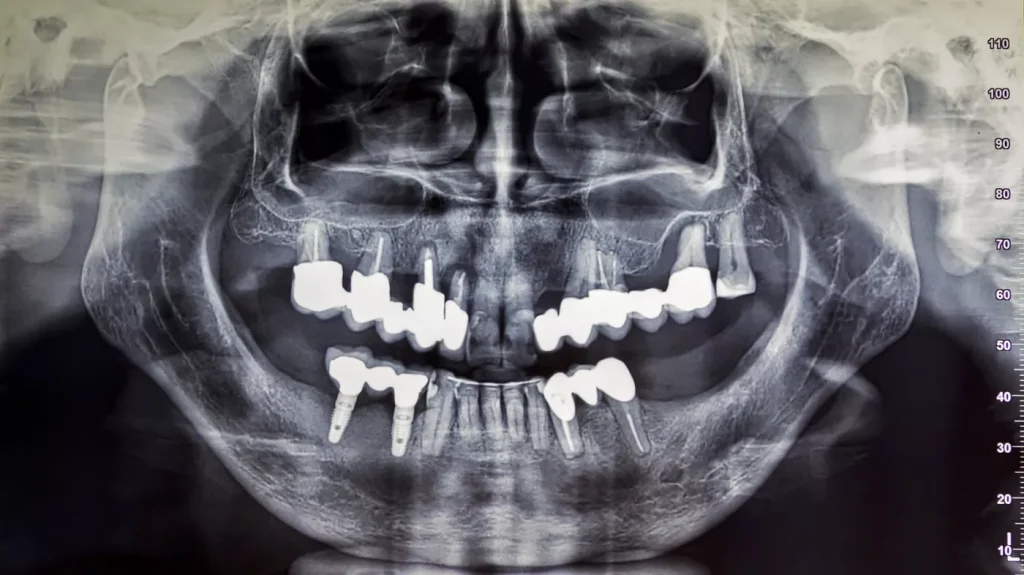

Echipamentul radiologic permite stomatologilor să identifice structurile orale interne, precum forma, dimensiunea, densitatea și textura dinților și a suportului lor de susținere. Aceste informații sunt cruciale pentru:

Foarte multe afecțiuni orale importante pot fi identificate cu ajutorul radiologiei dentare:

- Carii interdentare;

- Carii formate sub obturații (caria secundară);

- Infecția osoasă;

- Infecția pulpei dentare;

- Fractura dintelui;

- Pungi parodontale;

- Formațiuni tumorale;

- Resorbția osoasă;

- Dinți supranumerari;

- Dinți incluși (erupți în os);

- Periimplantita.

Cu ajutorul imaginilor obținute radiologic, medicul dentist îți poate oferi tratamentul și îndrumările potrivite pentru a îți rezolva toate afecțiunile orale.